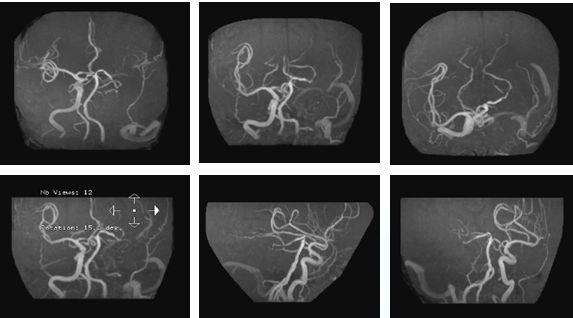

造影示:颈内动脉闭塞,眼动脉有代偿,血管闭塞原因决定血管再通方式!

找到闭塞血管部位,狭窄?夹层?

在颈内远端用6*30Solitaire逐次向近端释放支架(夹层可能性大)

支架释放状态血管通畅,逐渐找到血管闭塞部位

支架在病变最近端释放

11-3,21:40:血管再通,支架释放解脱